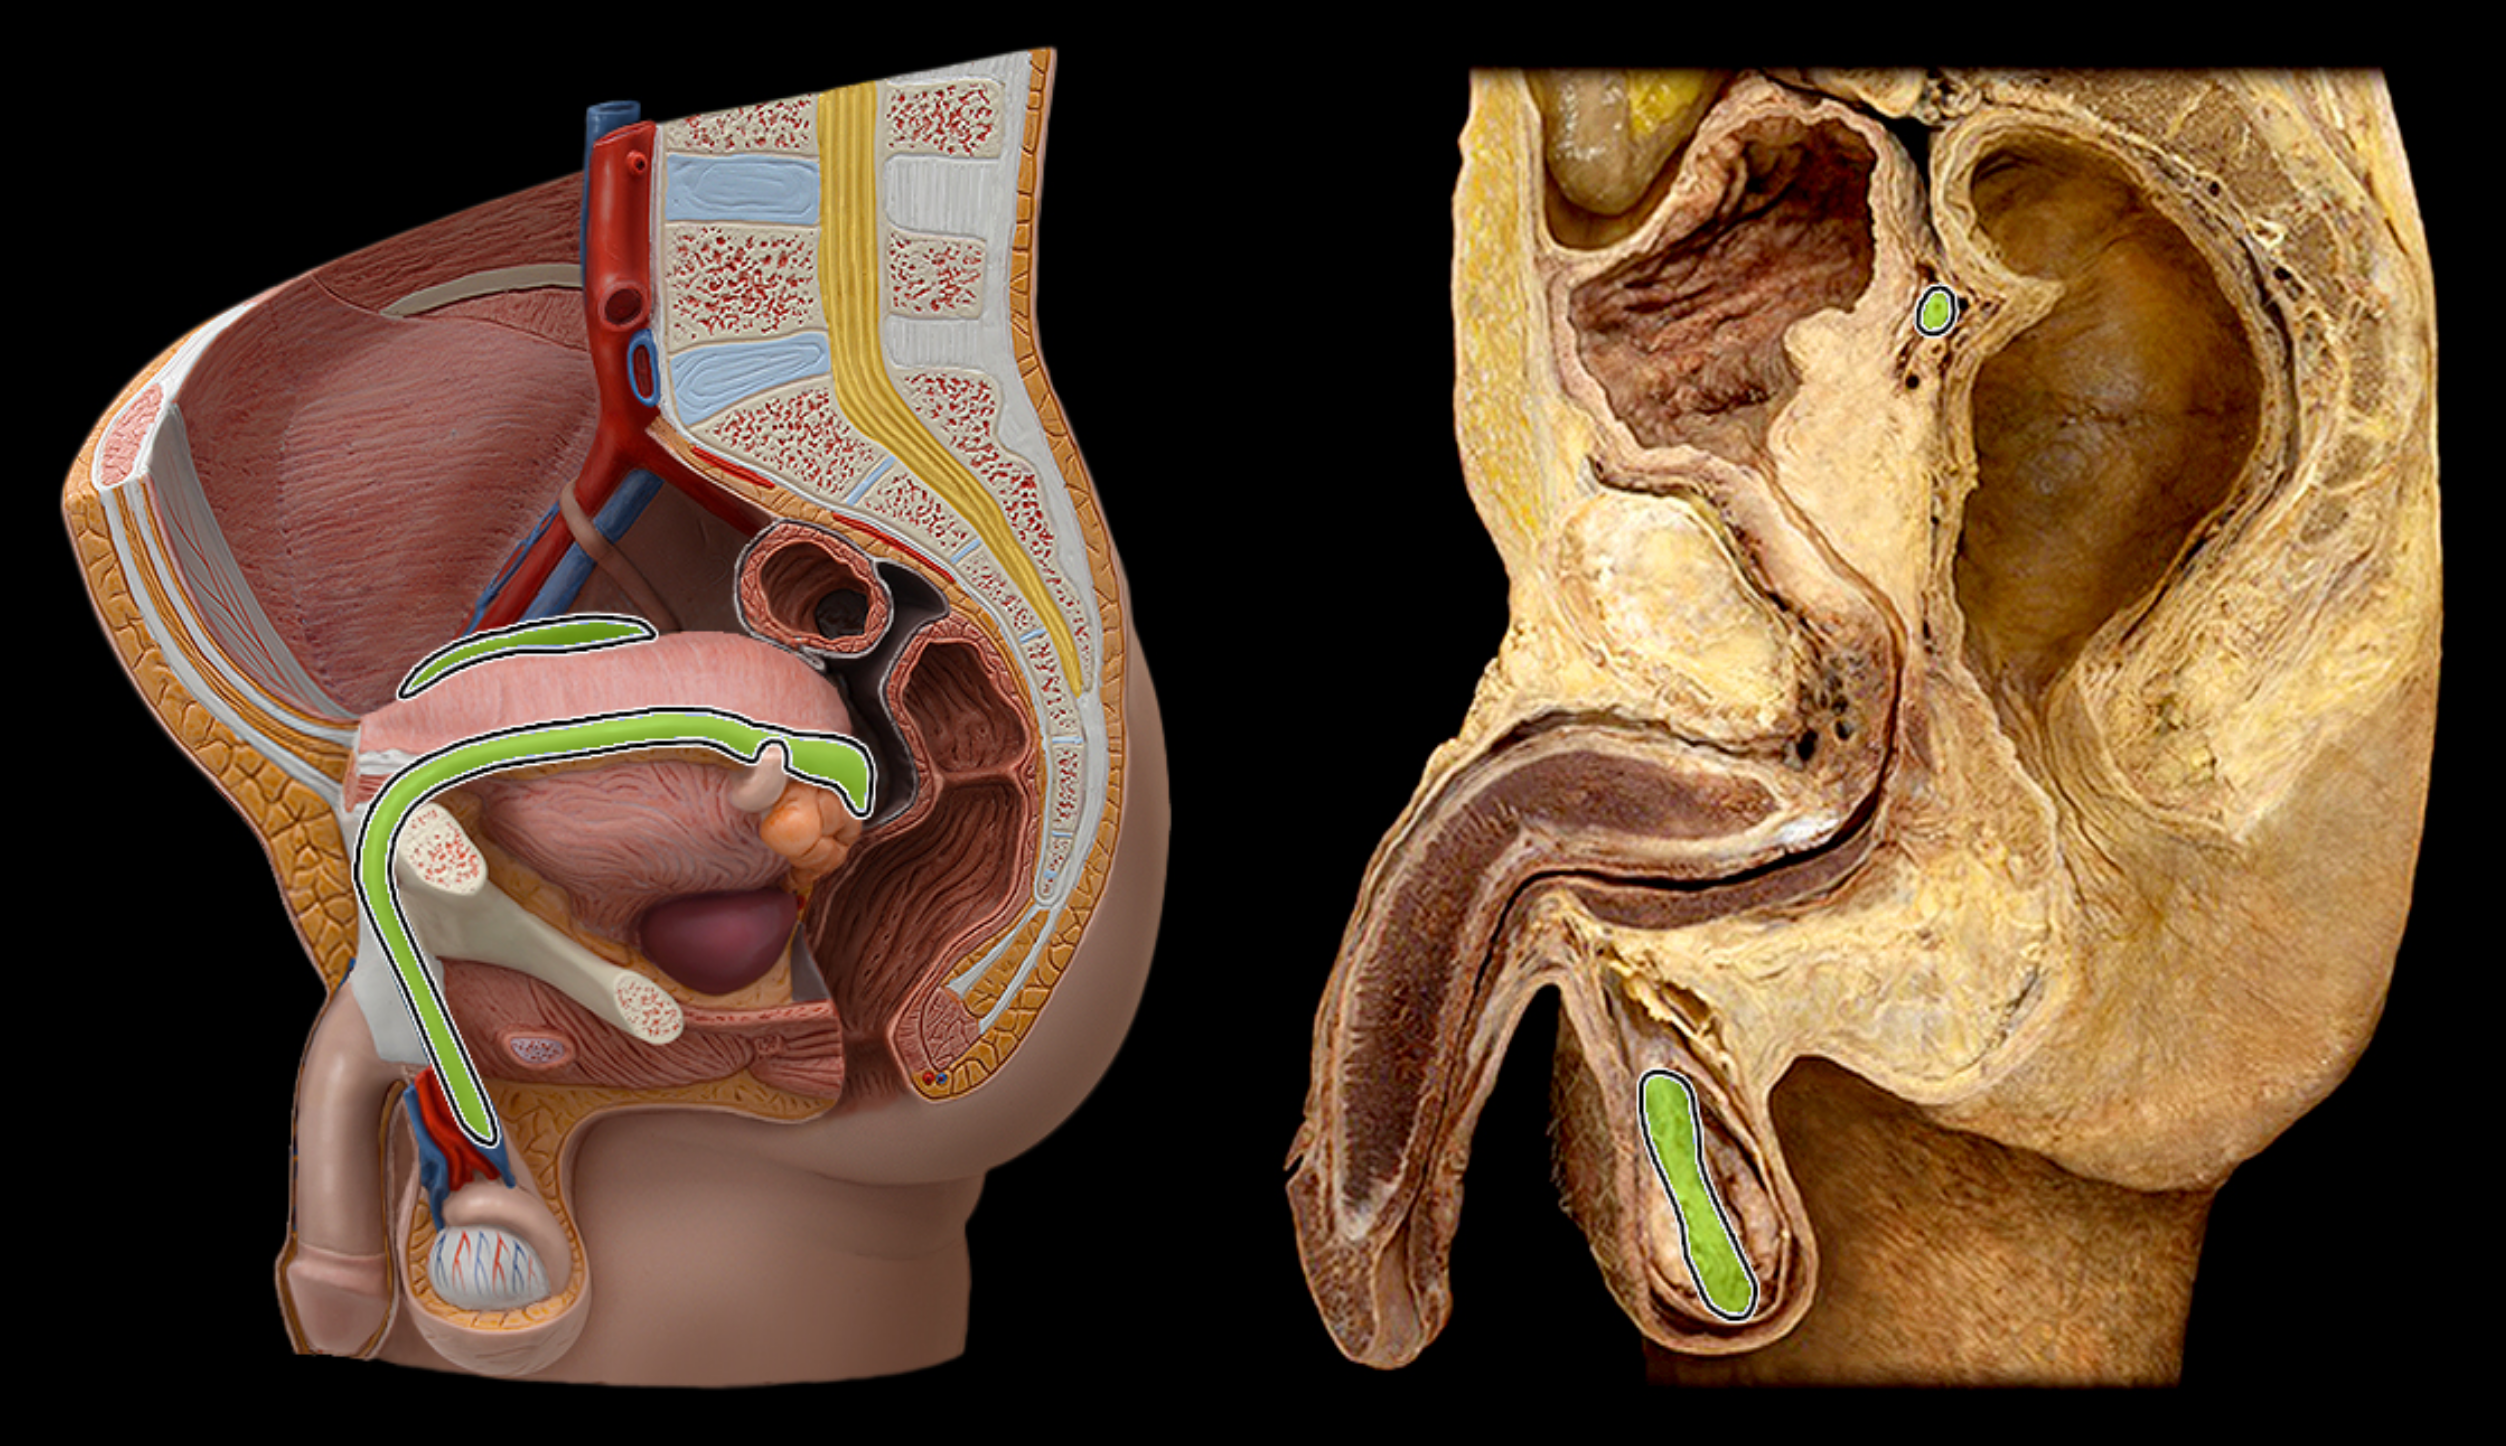

Vas deferens (ductus deferens)

Ejaculatory duct

Seminal vesicle